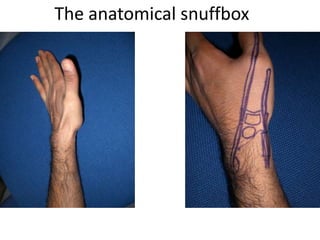

- Naming the bones, joints, tendons, nerves and skin landmarks of the hand and wrist.